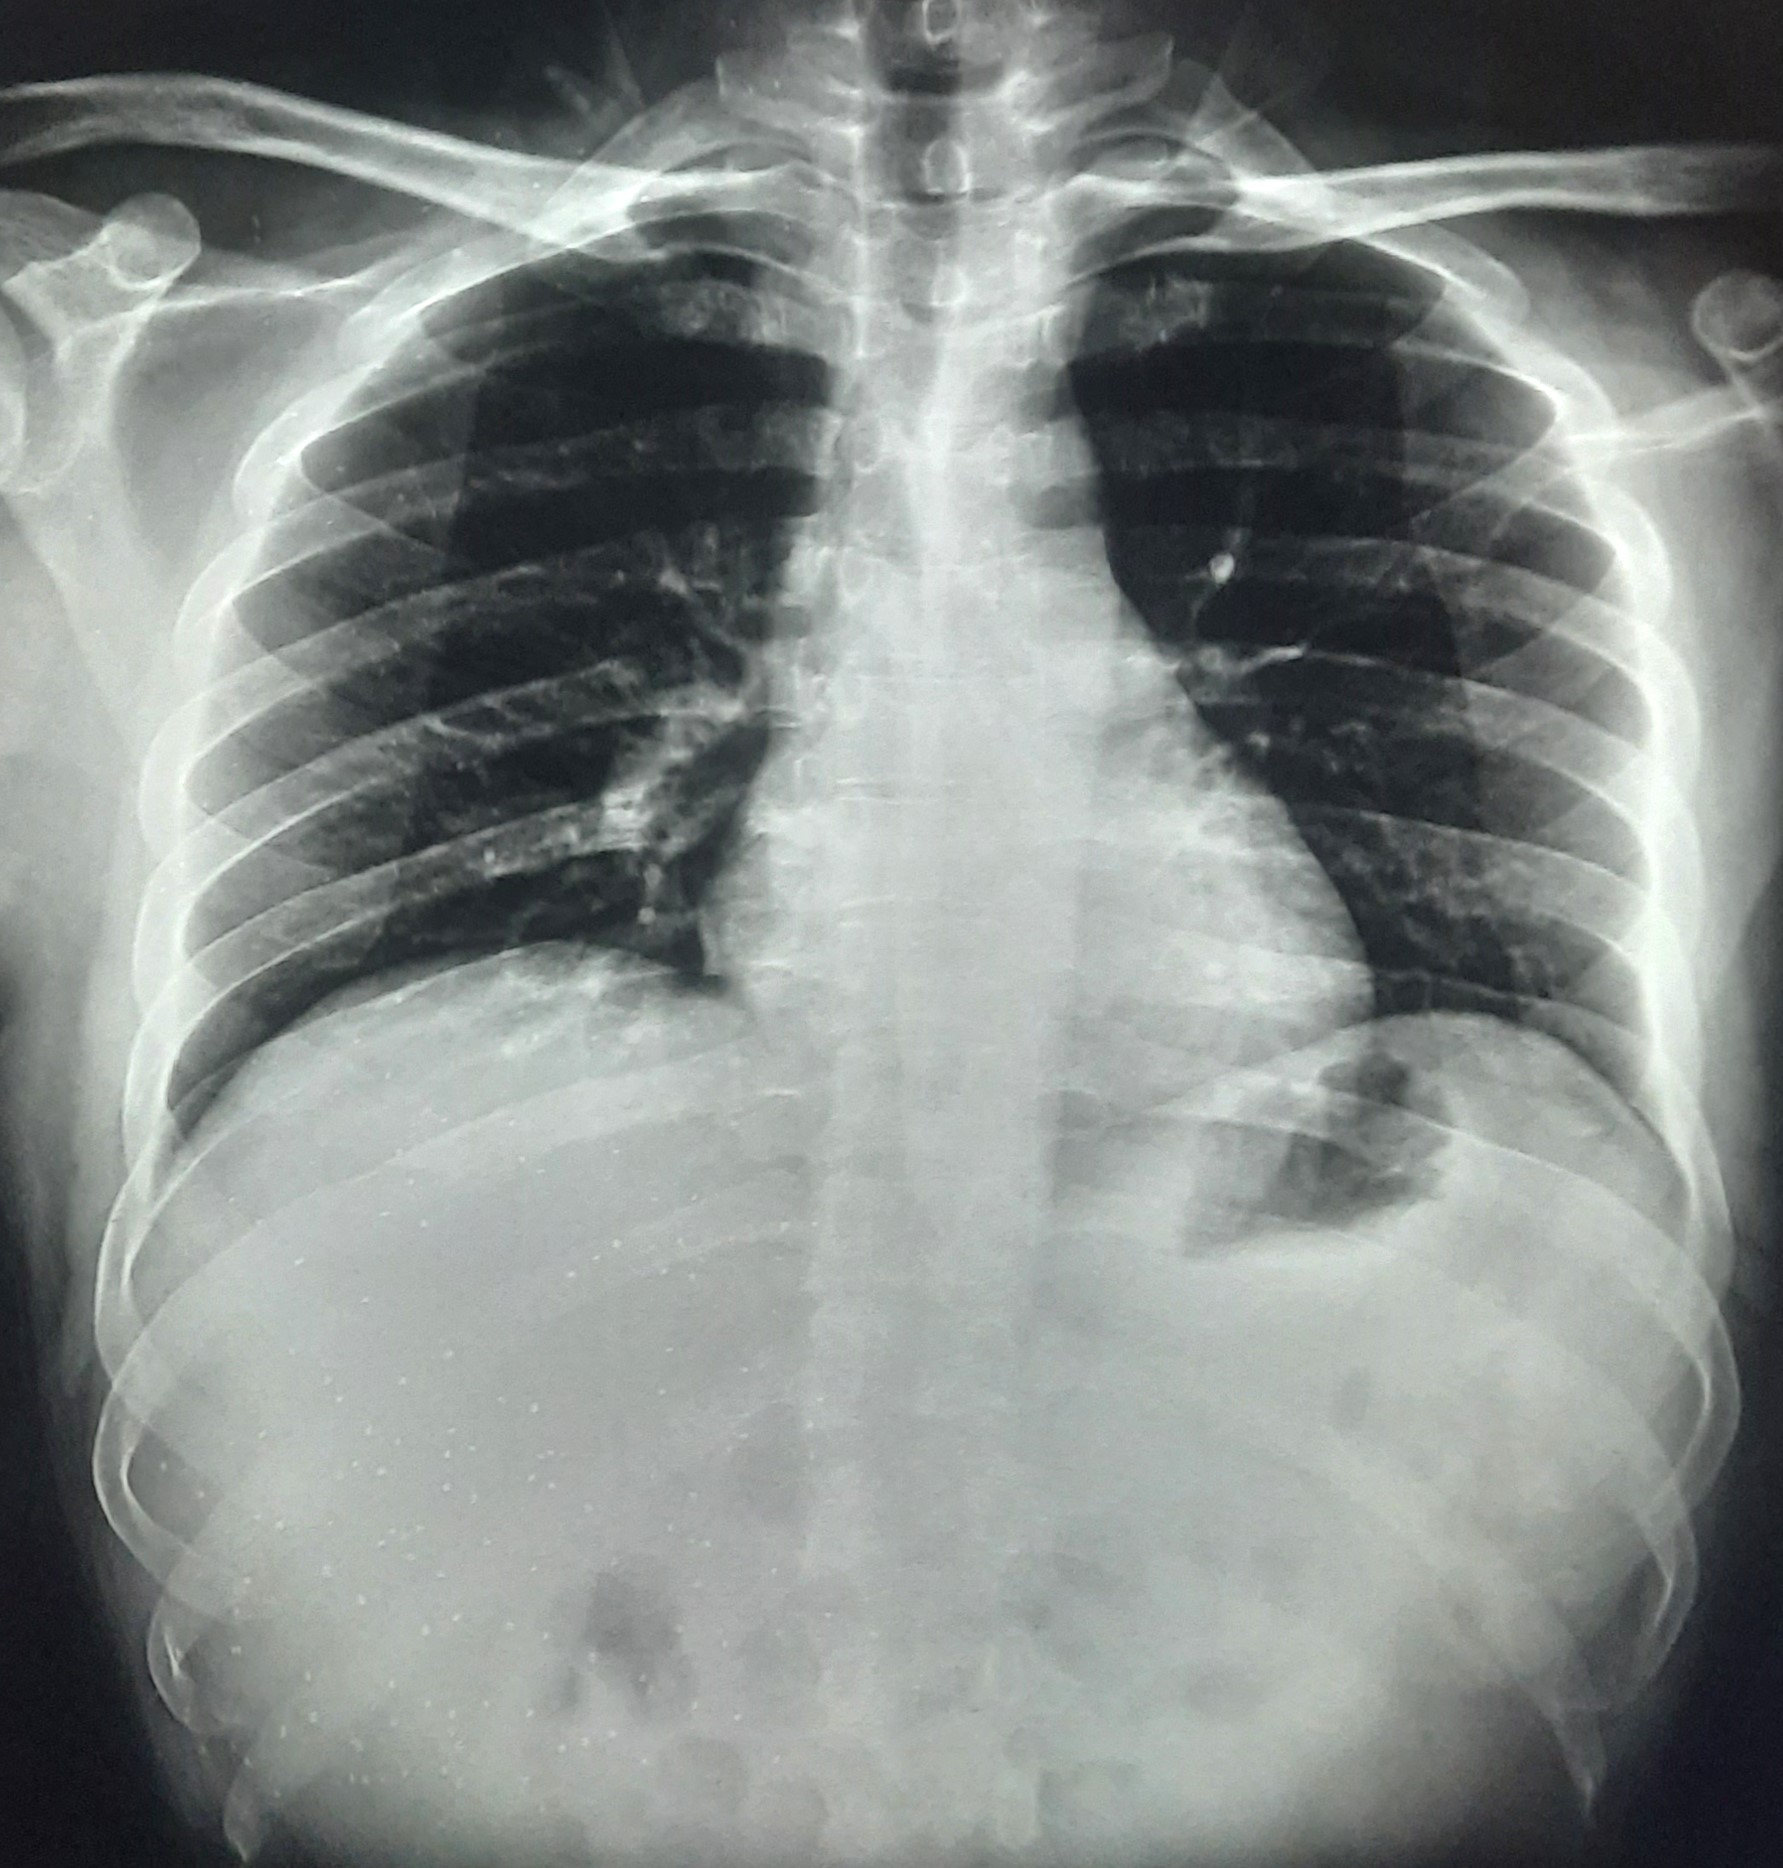

| 292 | IGGMC, Nagpur, Nagpur | P2 | 29-4180 | Geeta Bhonde | Consent taken on Paper | 52 Yrs. |

Provisional Diag : ?

Final Diag : Cardiomegaly |

Non-TB Case (Confirmed) | Abnormality visible on x-ray |